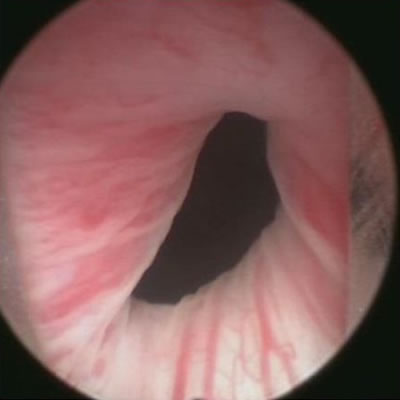

I nuovi laser in Urologia

In un forum internazionale di esperti tenutosi a Cipro, coordinato dalla Società Cipriota di Urologia, si è discusso tra le altre cose sull’utilizzo dei nuovi laser in urologia.

Questi strumenti ad oggi permettono il trattamento di numerose patologie urologiche maligne (tumori del rene, della vescica e della prostata) e benigne (calcolosi, ipertrofia prostatica benigna).

Tra i vantaggi più significativi dei nuovi laser - ha spiegato il Prof. Gacci - ci sono sicuramente la maggior potenza e quindi efficacia d’azione, associata ad una minor dispersione di energia e danno termico e di conseguenza una minor incidenza di effetti collaterali.

LA pratica quotidiana nell’utilizzo di tutti i laser disponibili da parte del chirurgo permette di padroneggiare tutte le tecniche e di personalizzare il trattamento, adattandosi alle esigenza di ogni singolo paziente.